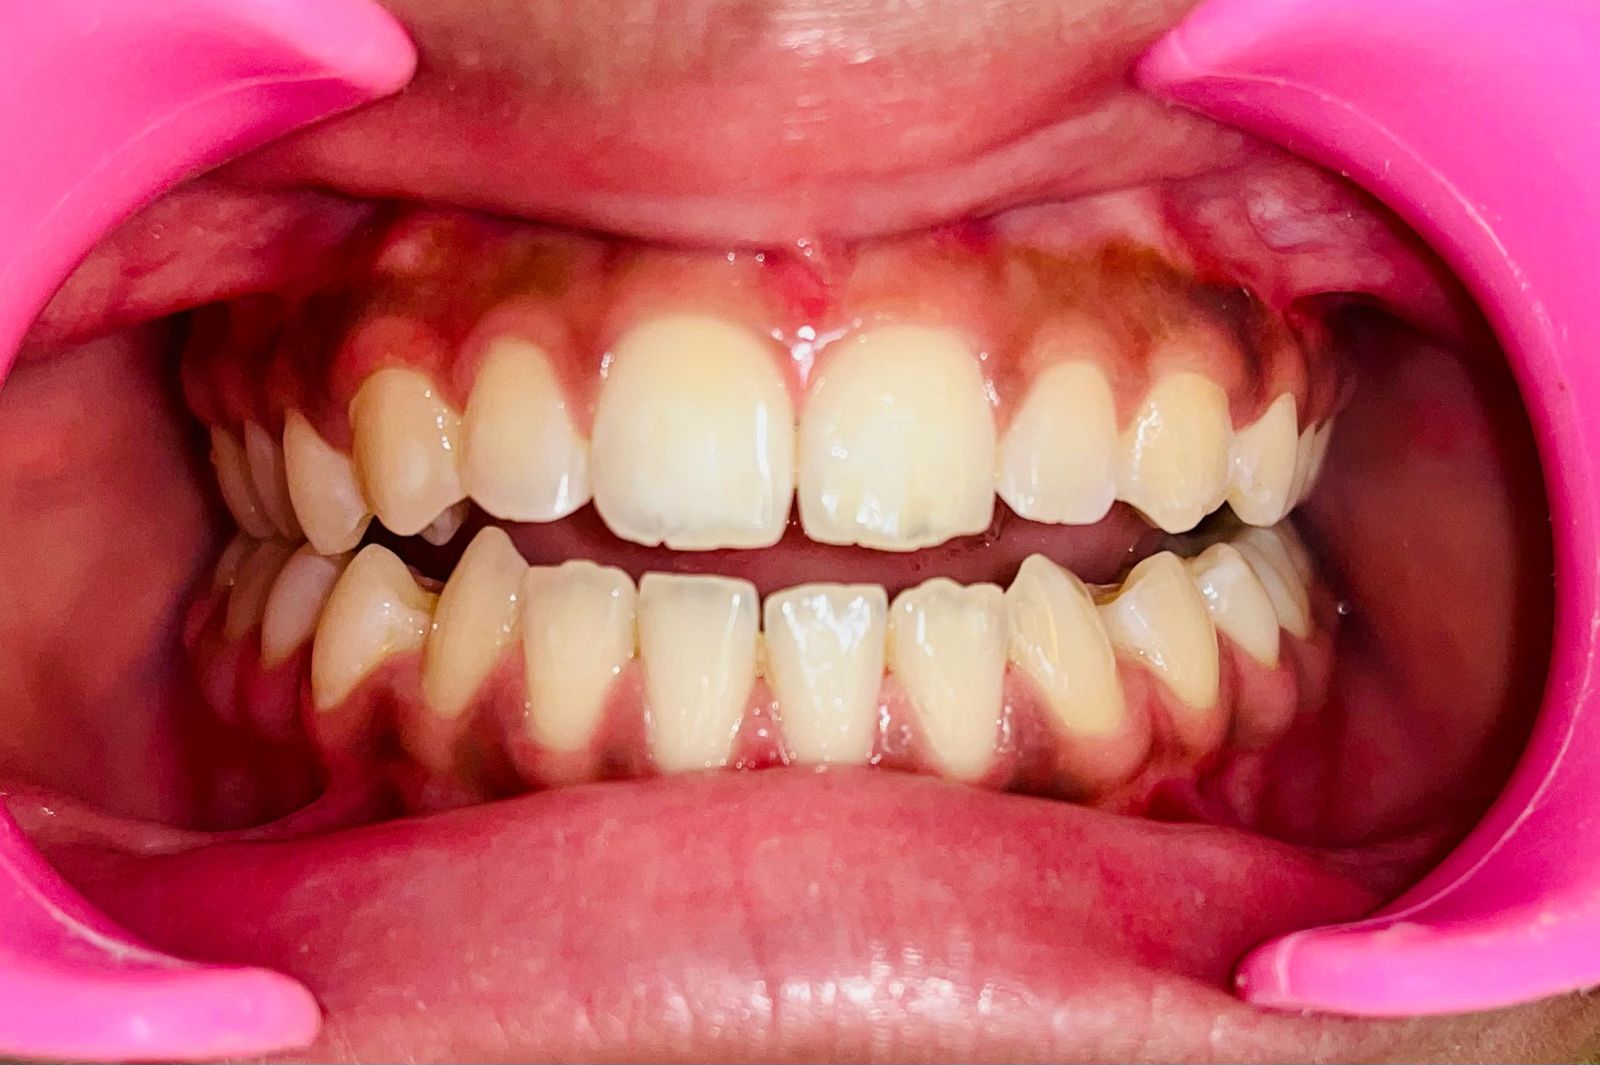

Clinical Success Stories

Real cases, remarkable transformations

Before Treatment

Before

After Treatment

After

Moderate Crowding Case

Duration: 11 months

Aligners: 25 sets

"I used to be so self-conscious about my 'open bite'—I couldn't even bite through a sandwich properly because my front teeth didn't touch. I was skeptical that clear aligners could fix something that looked so complicated, but I am so glad I went for it. It took about 11 months and 26 sets of aligners, and now my smile actually feels 'complete.' The process was so much easier than having metal braces, and finally being able to smile with confidence has been life-changing!" — Ananya M.